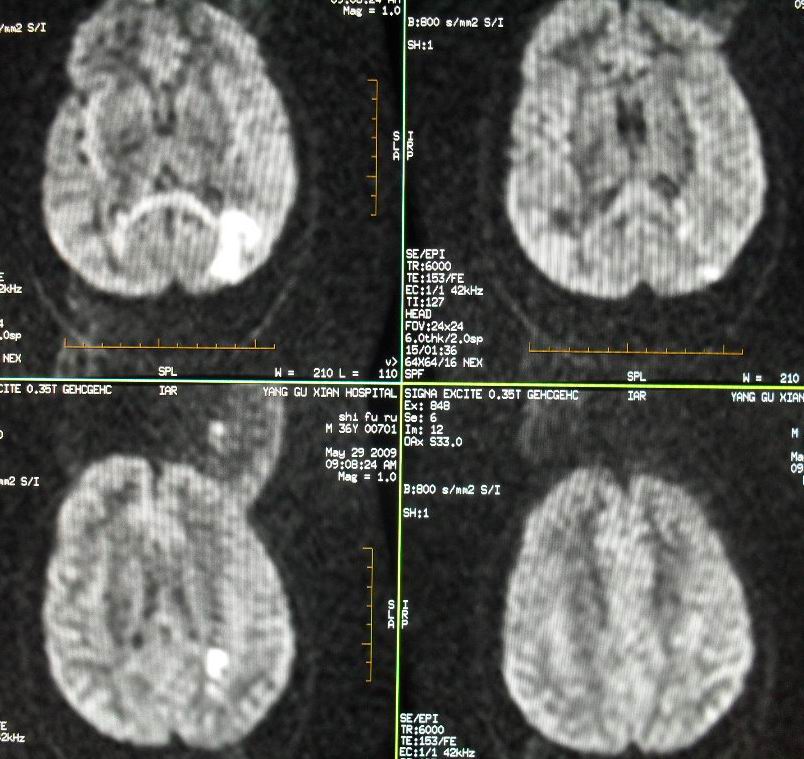

标题: 建议磁共振检查

[em1]